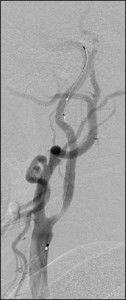

頸動脈ステント留置術(CAS)

![]() 1.ワイヤー通過 |

![]() 2.遠位遮断 |

![]() 3.ステント留置 |

ステント治療前 |

ステント治療後 |